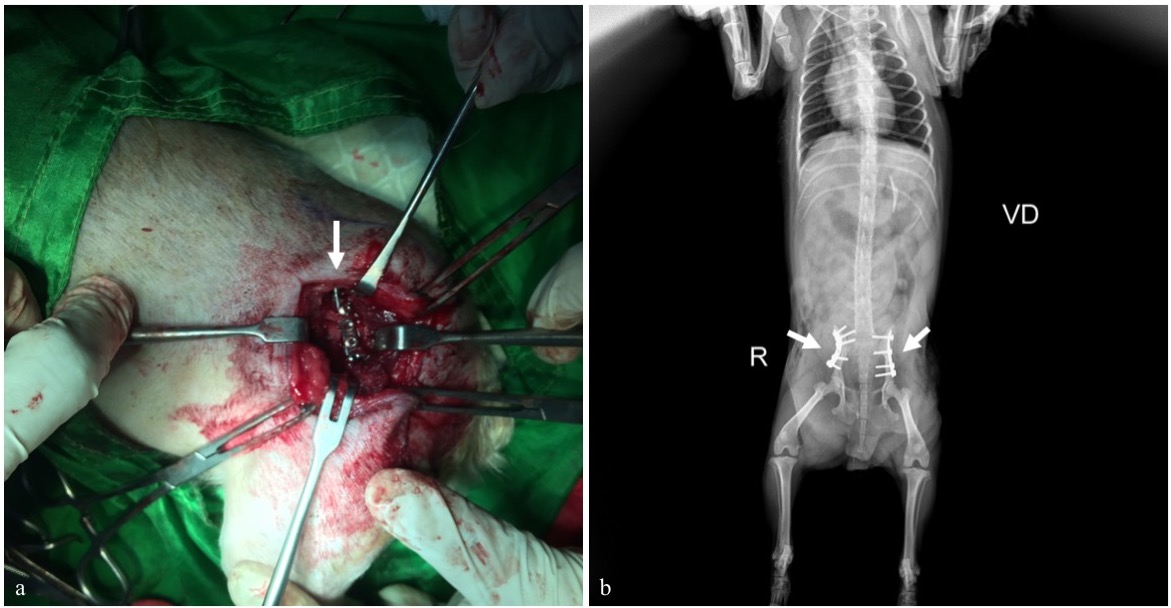

Fiksasi Internal secara Terbuka Fraktur Bilateral Pelvis pada Anjing Erwin Erwin; . Amiruddin; . Rusli; . Etriwati; Mustafa Sabri; Mulyadi Adam; Cut Erika Ramadhana; Afif Yuda Kusuma

Fraktur adalah terputusnya kontinuitas jaringan tulang yang umumnya disebabkan oleh trauma. Anjing ras Yorkshire berumur 2,8 tahun dengan bobot badan 2,6 kg menunjukkan gejala klinis tidak bisa berdiri, kedua ekstremitas posterior mengalami diplegic lameness dan anjing hanya bertumpu dengan ekstremitas anterior. Anamnesis dengan pemilik hewan mengatakan anjingnya mengalami trauma akibat tertimpa tangga. Hasil pemeriksaan radiografi dengan posisi hewan right lateral dan ventro dorsal menunjukkan fraktur bilateral pelvis berbentuk oblique pada tulang ilium. Penanganan yang dilakukan adalah dengan metode open reduction internal fixation menggunakan bone plate 2.0 veterinary cuttable plate (VCP) dengan screw 2.0 mm cortical non-self-tapping pada kedua sisi tulang ilium. Hari ke-3 setelah tindakan bedah, pasien mulai dibantu untuk berjalan sebagai upaya melatih pergerakan ekstremitas posterior. Satu minggu setelah bedah, pasien sudah bisa berjalan dan menunjukkan perkembangan yang baik. Penanganan bilateral fraktur pelvis berbentuk oblique pada bagian ilium dapat ditangani dengan bone plate dan screw.